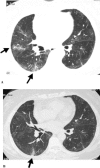

Results: Positive SARS-Co virus IgG antibody results were seen in 208 of 258 patients, with 21.3% (55 of 258 patients) still having a pulmonary diffusion abnormality (D(LCO) < 80% of predicted). By comparing the 155 survivors with positive SARS-CoV IgG antibody results and D(LCO) > or = 80% predicted with the 50 patients with negative SARS-CoV IgG results, we found that 53 patients with positive SARS-CoV IgG results and a lung diffusion abnormality had endured a much longer course of fever and received larger doses of glucocorticoid, as well as higher ratios of oxygen inhalation and noninvasive ventilation treatment. For these patients, 51 of 53 patients with positive SARS-CoV IgG results and a lung diffusion abnormality underwent pulmonary function testing after approximately 1 month. D(LCO) improved in 80.4% of patients (41 of 51 patients). Of the patients with a lung diffusion abnormality, 40 of 51 patients showed lung fibrotic changes in the lung image examination and 22 patients (55%) showed improvement in lung fibrotic changes 1 month later.

Conclusion: These findings suggest that lung fibrotic changes caused by SARS disease occurred mostly in severely sick patients and may be self-rehabilitated. D(LCO) scores might be more sensitive than HRCT when evaluating lung fibrotic changes.